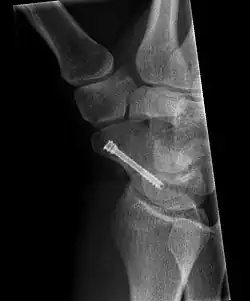

Scaphoid fracture before and after operation

The scaphoid can be slow to heal because of the limited circulation to the bone. Fractures of the scaphoid must be recognized and treated quickly, as prompt treatment by immobilization or surgical fixation increases the likelihood of the bone healing in anatomic alignment, thus avoiding mal-union or non-union.[6] Delays may compromise healing. Failure of the fracture to heal ("non-union") will lead to post-traumatic osteoarthritis of the carpus.[1]: 189  One reason for this is because of the "tenuous" blood supply to the proximal segment.[3] Even rapidly immobilized fractures may require surgical treatment, including use of a headless compression screw such as the Herbert screw to bind the two halves together.